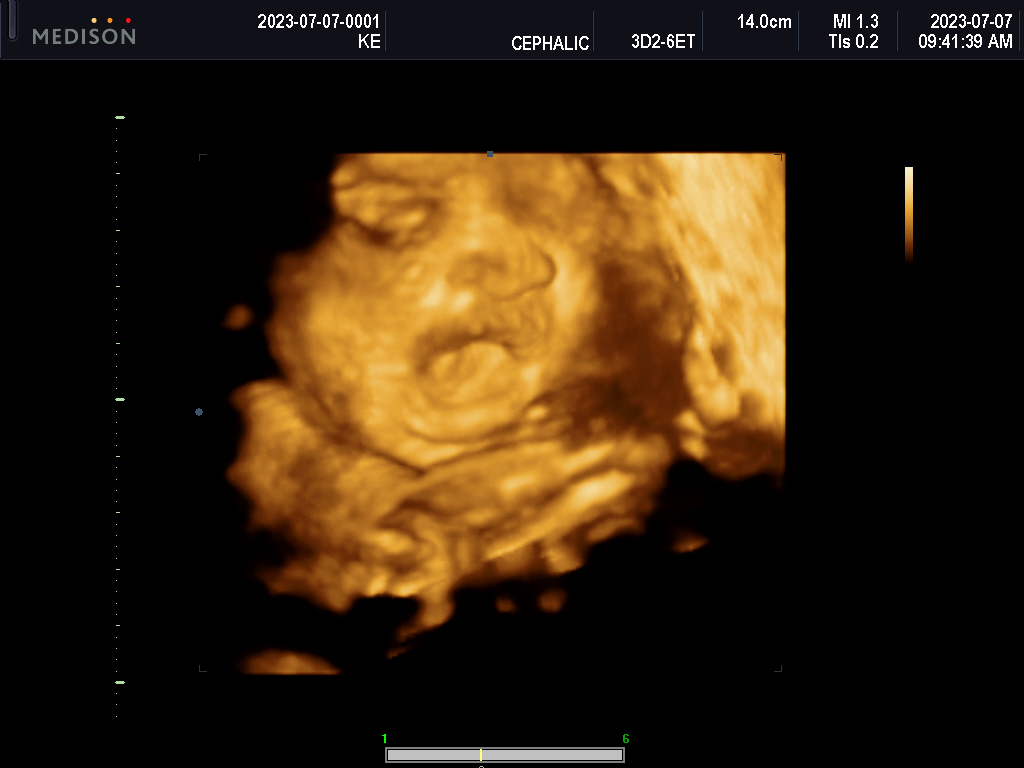

What will she look like?

What parts of us will she carry?

Will she have Nono’s forhead? FIFI’s stubbornness?